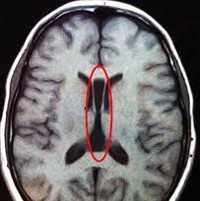

Основной метод диагностики ФКД — магнитно-резонансная томография. Она должна выполняться по специальному протоколу с толщиной срезов 1-2 мм. Только такое тщательное сканирование способно выявить минимальные структурные изменения мозговой коры. В МРТ диагностике корковой дисплазии имеет значение опыт и квалификация рентгенолога. Поэтому при необходимости результаты исследования следует показать более опытному в этом вопросе специалисту.

К МРТ признакам ФКД относятся: локальная гипоплазия или утолщение коры, «смазывание» перехода между белым и серым веществом, изменённый ход извилин, повышенный МР-сигнал на ограниченном участке коры при исследовании в режимах Т2 и FLAIR. Каждый тип ФКД имеет свои особенности МРТ-картины.

В обязательно порядке пациентам с ФКД проводится электроэнцефалография. В большинстве случаев она выявляет очаговую эпилептическую активность мозга не только в момент приступа, но и в межприступный период. Во время приступа отмечается повышенная возбудимость и активация зон коры, прилежащих в визуализируемому на МРТ очагу дисплазии. Это связано с наличием аномальных клеток и за пределами основного участка корковой дисплазии, который является лишь «верхушкой айсберга».